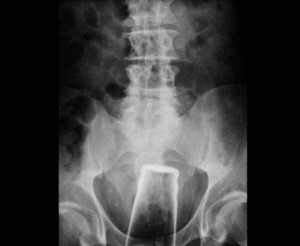

ჭიქა

3 (1)